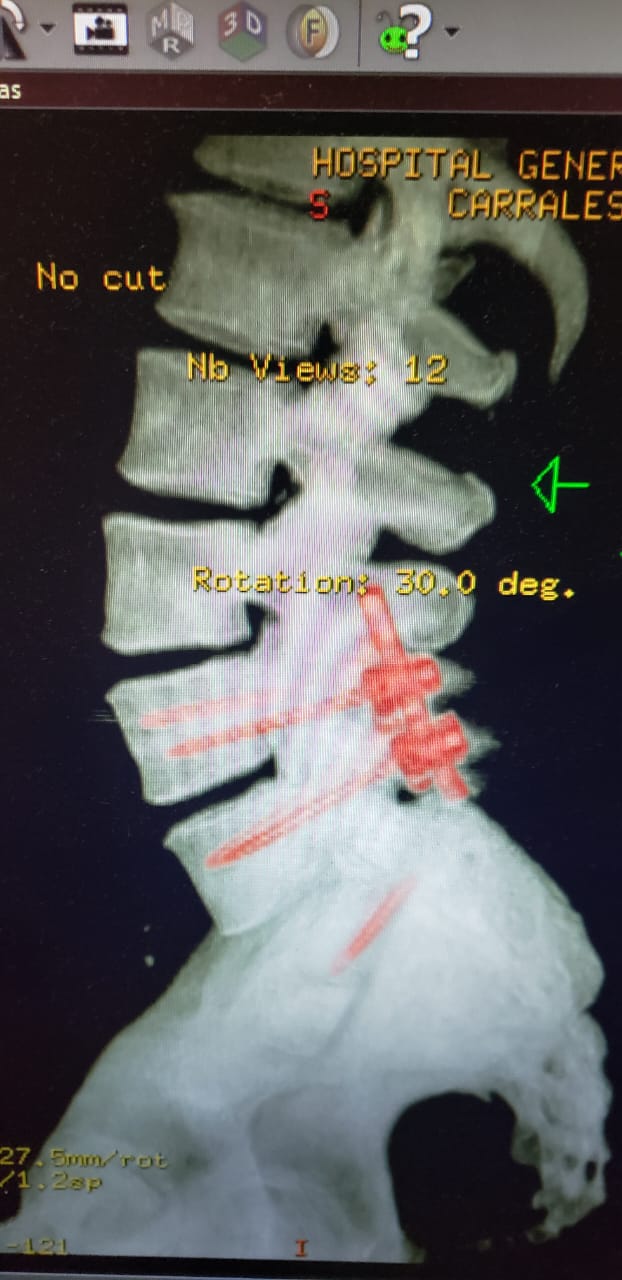

Colocación De Tornillos Para Corregir Listesis Lumbar

Servicio especializado en la estabilización de la columna lumbar mediante la colocación de tornillos pediculares, con el objetivo de corregir el desplazamiento vertebral (listesis) y aliviar los síntomas neurológicos asociados.

Busca restaurar la alineación espinal, mejorar la función y calidad de vida del paciente, mediante técnicas quirúrgicas seguras y de alta precisión.